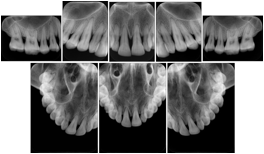

3. A dental provider wishes to capture a series of DICOM IO images for the patient’s dentition. The tooth morphology, teeth are divided into molars, premolars, canines and incisors, and a number of images for each jaw. The anatomic information was captured utilizing the triplet of schema. This standard code sequence is based on ISO 3950-2010, Dentistry - Designation system for teeth and areas of the oral cavity.

Every IO image should have anatomic information either through the primary or modifier sequence.

In most standard cases, images are oriented in structured layouts. These structured displays are useful to be shared between providers for reference purposes.

Table OO.1.1-1 shows structured display standard templates, where Viewset ID is based on the Japanese Society for Oral and Maxillofacial Radiology (JSOMR) classification provided by JIRA (Japan Medical Imaging and Radiological Systems Industries Association, www.jira-net.or.jp). Expected or typical teeth to be imaged location, region and designation codes are based on ISO 3950-2010, Dentistry - Designation system for teeth and areas of the oral cavity. For all the hanging protocols listed in OO.1.1-1, the value to use for Hanging Protocol Creator (0072,0008) is "JSOMR" and the value to use for Hanging Protocol Name (0072,0002) does not include "JSOMR" (e.g., "DL-S001A", not "JSOMR DL-S001A").